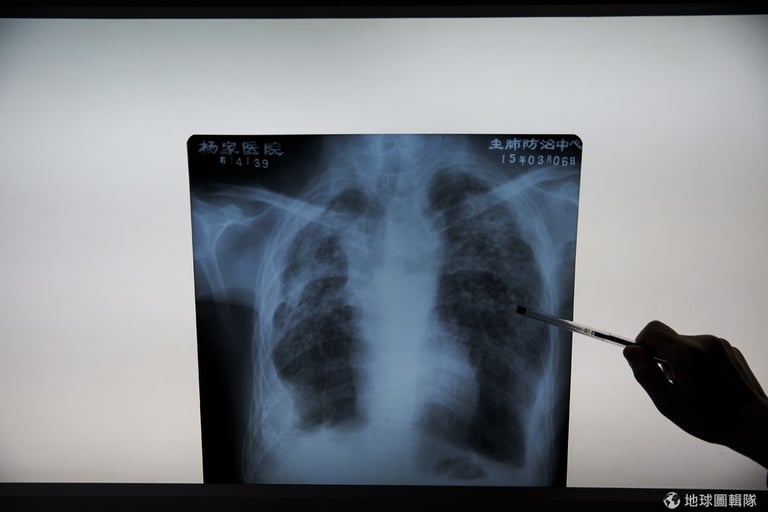

傅劍華院長正透過X光片解說罹患矽肺病患者的典型症狀。

楊家醫院並非一開始就是這樣殘破的樣貌, 1980年代時,這裡曾是治療肺病首屈一指的醫院,院內醫護人員多達 150位,當時這裡還配有日本來的最先進X光檢查設備,但隨著病人數減少缺乏收入,外加政府沒有太多支援下,如今的楊家醫院只剩蔓藤叢生的淒涼。2001年時,醫院宣告破產後就轉由公家機關管轄。